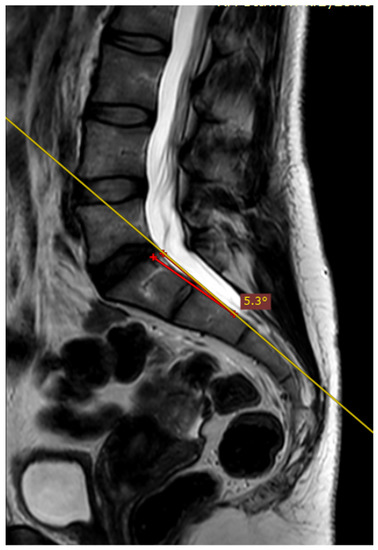

The deviation angles were measured on T2-weighted sequence slices obtained in the sagittal plane, as shown in Figure 1. Figure 2, presented below, shows the interrelationship of the three sequences of the same examination (as shown in Figure 1) that were used in this study. The RadiAnt DICOM Viewer was used to take measurements. All examinations were analyzed by two independent researchers in a blind study. The final results of the measurements were averaged to obtain a single deviation angle corresponding to each examination.

Figure 1.

The measured deviation angle equals 5.3 degrees (group 2). The red line is the fully correct line drawn between the posterior edges of the S1 and S2 vertebrae. The yellow line marks the actual plane in which the slices were acquired.